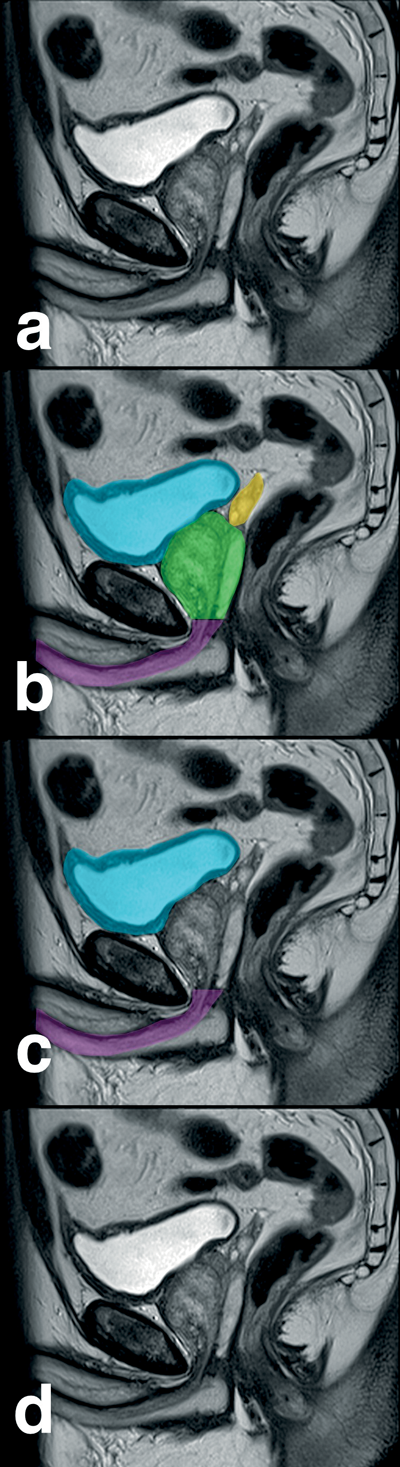

In certain circumstances, you may wish to annotate or even add coloured shading to cross-sectional images to illustrate anatomy and subsequently incorporate them into a video sequence. Using Keynote (as above), we create a ‘custom’ sized slide to match the size of the radiological image, which is shown on the file attributes e.g. 512 x 512. We then ‘drag and drop’ the relevant cross-sectional images into Keynote which then automatically creates individual slides from each image. The relevant slides are now annotated with text or the relevant anatomical detail may be outlined with a Keynote drawing tool. At this point, it is important to note that any shape made with a drawing tool may be filled with colour and this colour shading may be either as a solid block of colour or made to have various degrees of transparency to allow anatomical detail to be seen through the shading. This technique is particularly useful when demonstrating surgical anatomy. In order to make annotations more obvious, it is sometimes worthwhile duplicating plain image slides just before and after the annotation starts or changes and this makes the annotation stand out (Figure 5).

Figure 5: Anatomical annotation of radiological images as Keynote slides (a - d)

with transparent colour shading. Sequential slides are exported as a QuickTime movie.

When annotations are completed, we choose a ‘dissolve’ transition between the slides and then export the slides as a QuickTime movie. This video sequence is now imported into the browser window of Final Cut.